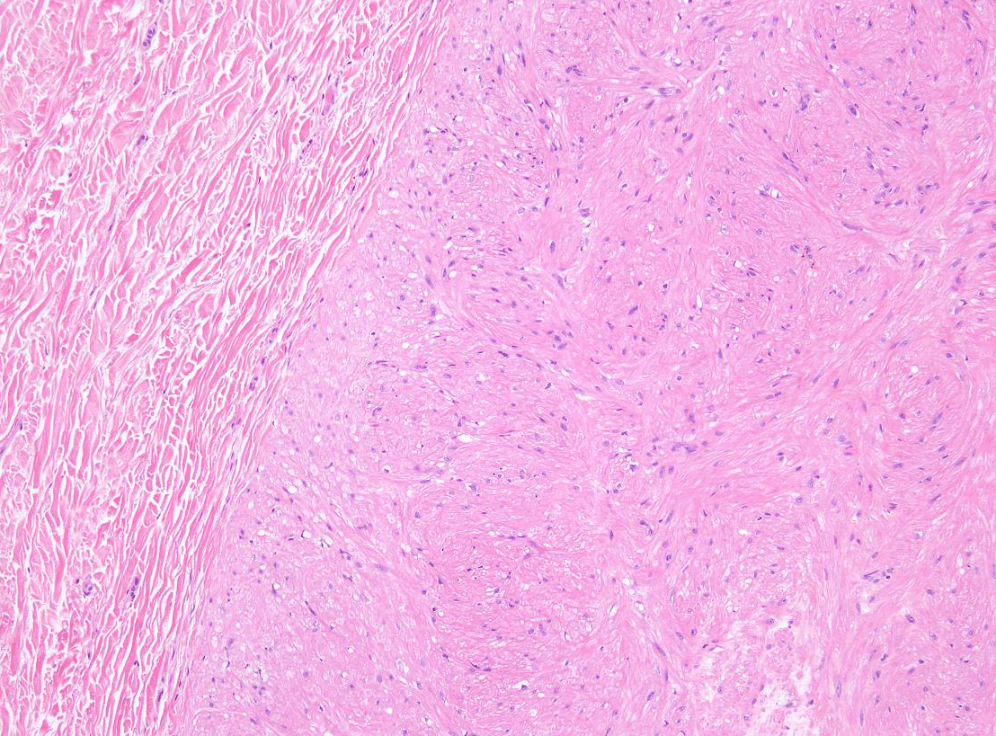

endometrial cancer